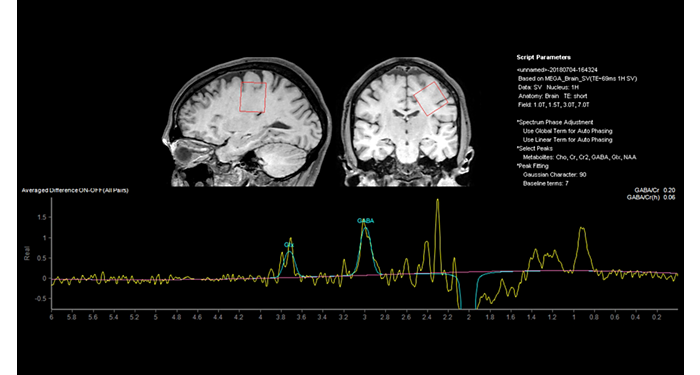

El 70% de los radiólogos consideran que las indicaciones neurológicas son un desafío, sobre todo debido a la falta de técnicas apropiadas de imagenología y visualización¹. Philips tiene como objetivo proporcionar la mejor claridad de diagnóstico posible y orientación terapéutica para todos los pacientes con trastornos neurológicos. Al aprovechar nuestra plataforma digital dStream, este año presentamos un conjunto de estrategias nuevas de imagenología y visualización. Esto puede ayudarlo a resolver preguntas sobre neurología complejas con mayor certeza, así como a desbloquear nuevos territorios neurológicos en aplicaciones neurofuncionales avanzadas. Este es un paso clave para aumentar el diagnóstico neurológico y, en última instancia, impactar más vidas con la RM. ¹ TMTG Market Survey 2016

Nuevas aplicaciones neurológicas

Protocolos cerebrales de UVM actualizados con los últimos métodos

UVM aprecia los últimos métodos neurológicos de resonancia magnética para el diagnóstico y el flujo de trabajo.